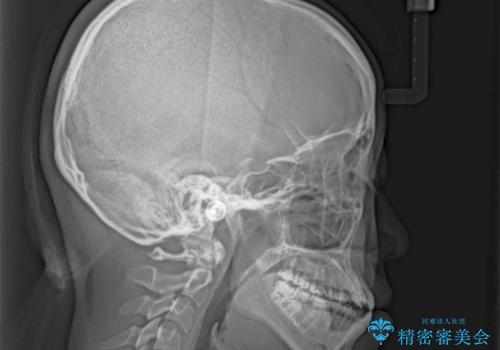

- 前歯のデコボコと、下顎の変位と受け口を気にして来院された患者様です。

初診時には大学病院にて顎の骨を切る外科矯正を勧めましたが、妥協的なゴールでも構わないので外科処置をせずに矯正を行いたいとのことでした。

まずは急速拡大装置にて上顎骨を側方に拡大し、インビザラインにて歯列と咬合を整えることとしました。

上顎骨を拡大したことで、下顎の歯列を上顎が受け入れられるようになりましたが、インビザラインでは咬み合わせを改善させることができなかったため、ワイヤー矯正にて仕上げることとしました。